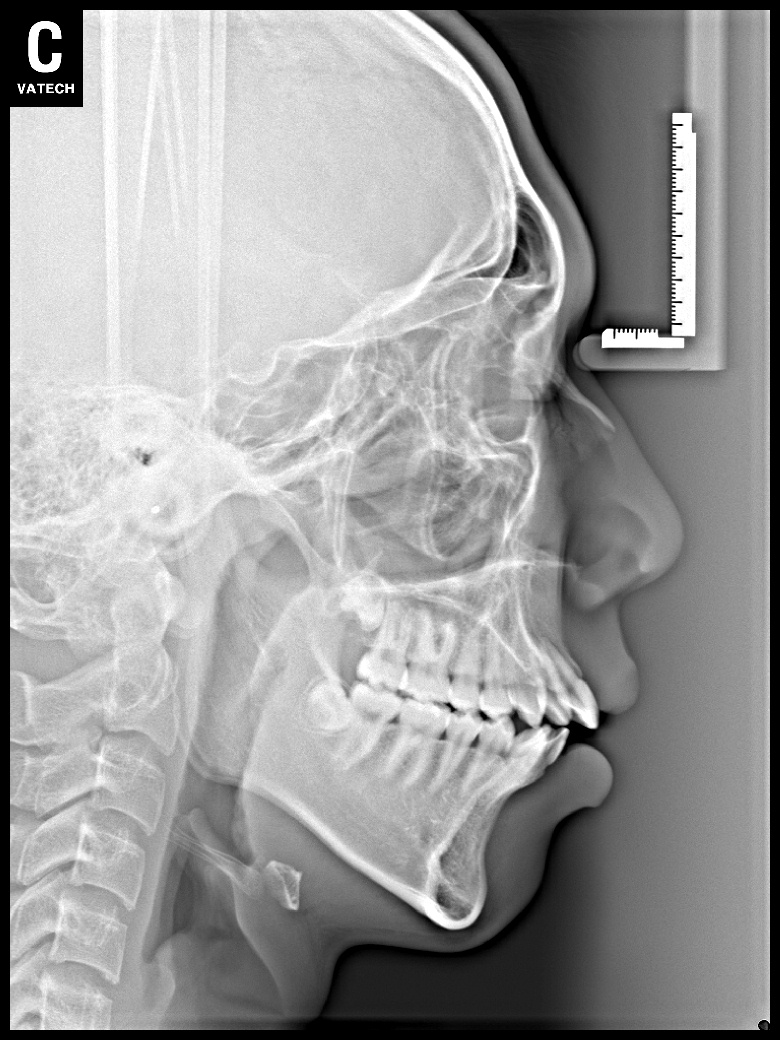

치료 전 사진입니다.